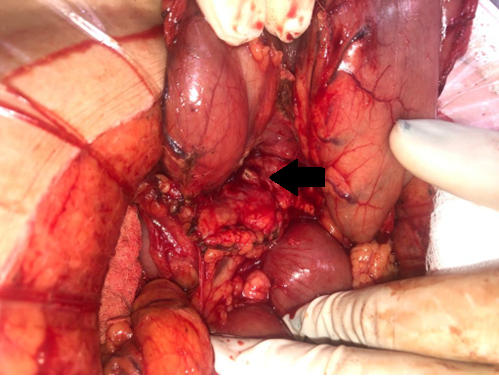

Abierto el peritoneo, no se identifica liquido intra abdominal ni citoesteatonecrosis. Se realiza la apertura de la transcavidad de los epiplones (figura 2) donde se identifica absceso retrogástrico. Se toma muestra para cultivo bacteriológico. Se identifica perforación gástrica de aproximadamente 5mm en cara posterior antral y lesión puntiforme pancreática en cuerpo. Se palpa cuerpo extraño (escarbadientes) a nivel antral, adyacente a la perforación. Se realiza antropiloroduodenotomia longitudinal, donde se evidencia la perforación en cara posterior del estómago. Se extrae cuerpo extraño, con cierre a la Heineke Mikulicz (figuras3y4). Rafia de perforación antral posterior con hilo reabsorbible, poliglactina 910, punto “en X”.

Figura 2: Apertura de la transcavidad de los epiplones. Estomago rebatido hacia arriba. Flecha negra indica perforación pancreática.